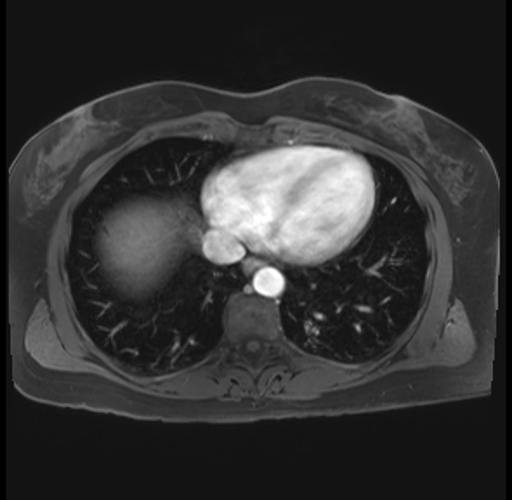

Imaging Analysis

Look through the patient's CT scan to identify any areas of concern for the necessary procedure.

Based on your CT findings, which issue(s) are present and would give reason for "planned slowing down moment(s)" in this case?